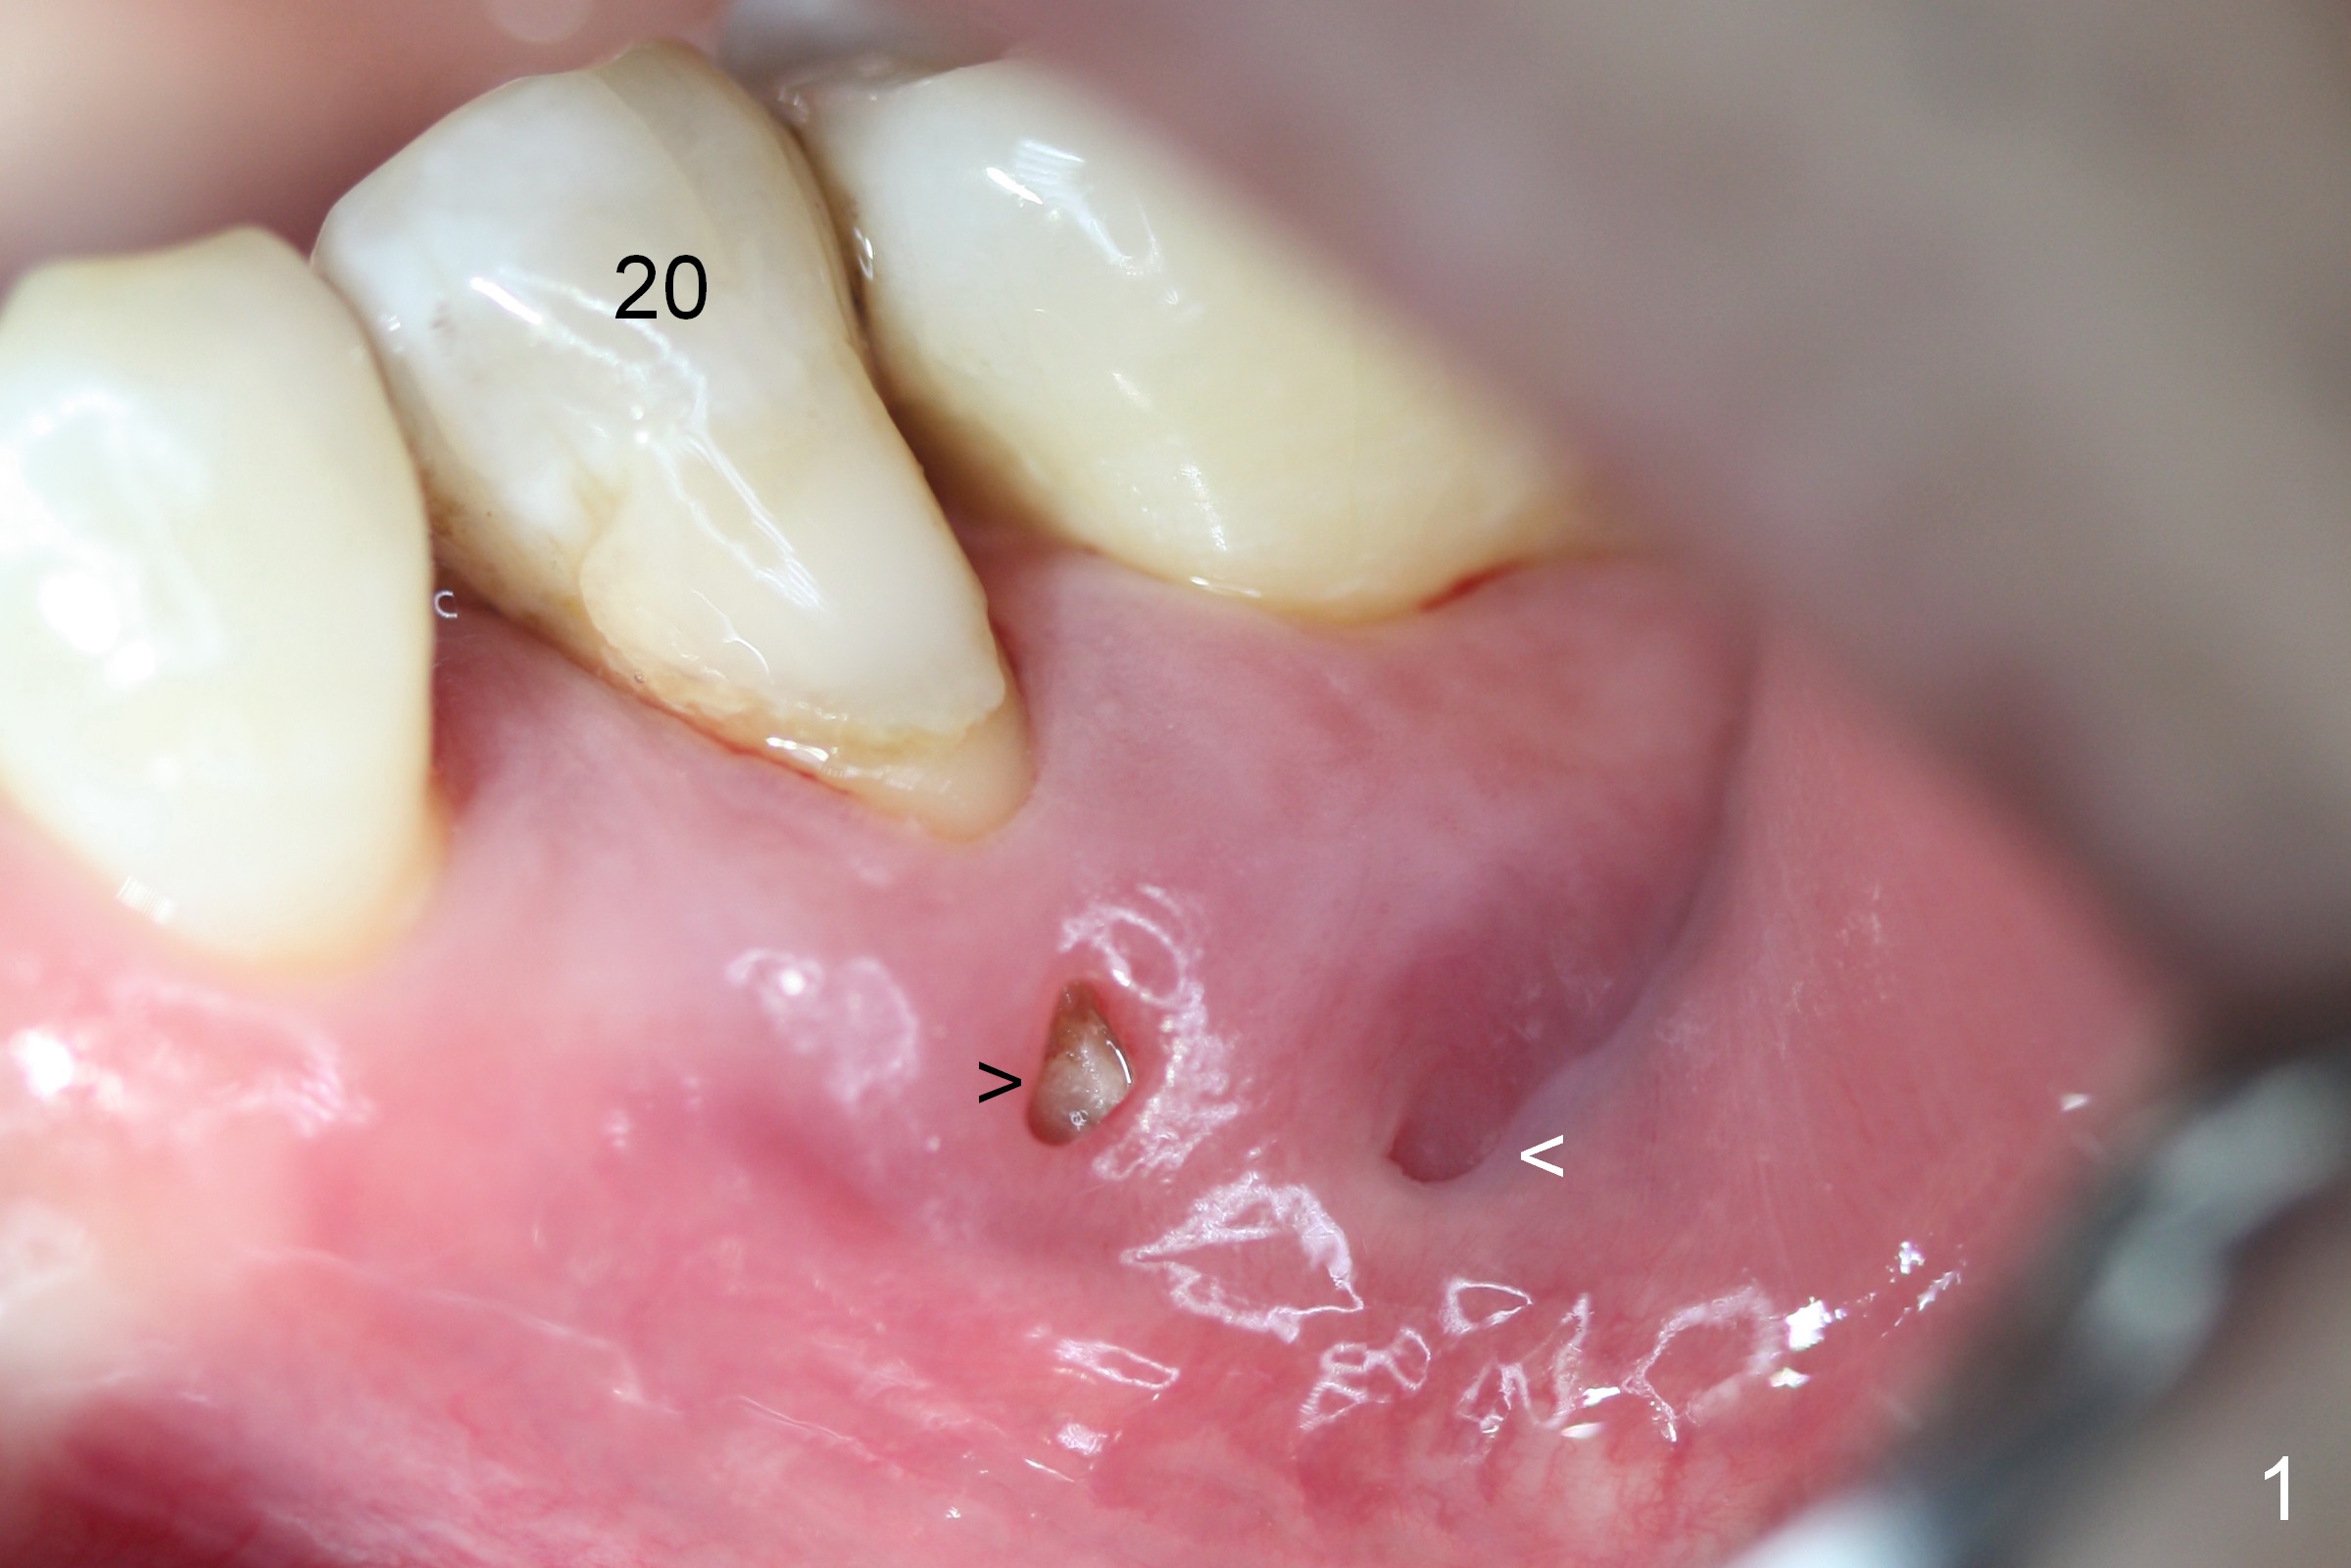

A 45-year-old man (JT) has endo failure at #20 with fenestration (Fig.1,2 black >) and fistula (white <). Insertion of a Gutta Percha at the fistula (Fig. 3 <; PA taken 2 years ago) indicates that the infection is dervied from the apex of the tooth #20. The socket will be soaked with 2% Xylo, 1:50,000 Epinephrine gauze. A 4.5x17 mm tissue-level (Fig.4) or 14 mm bone-level implant is placed as lingual as possible (Fig.5 green). If primary stability is achieved, an abutment is placed (pink). A large piece of resorbable membrane is used to cover the buccal defect (including buccal recession, fenestration and fistula (Fig.6 yellow dashed line). Two small pieces of non-resorbable membrane are placed to cover the gingival recession and the fenestration (Fig.7 white dashed line, buried underneath the edge of the gigniva). Then place bone graft buccally. Place a small piece of gauze (one layer) or plastic (from Tatum implant bag) over the 2nd membrane over the gingival recession and fabricate an immediate provisional. When the acrylic is partially set, remove the gauze or plastic from the provisional. After trimming and polishing, the provisional is cemented to securely keep the 2nd membrane in place. When the wound is healing and the 2nd membrane is stable, trim the buccal extension of the provisional. It is expected that the buccal hard and soft tissue will regenerate over the implant.